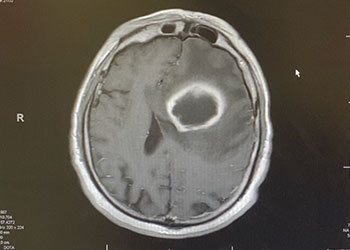

A teenage boy presented with 6 months of weight loss and difficulty swallowing. A contrast-enhancing mass in the brainstem and upper cervical cord was found which was suspicious of a symptomatic hemangioblastoma (Figure 1).

Symptoms from the slowly growing tumor stem from mass effect caused by the cystic component and the tumor. Contrast-enhanced brain MRI shows a hypervascular tumor. However, the exact location of the tumor in terms of intra- or extramedullary or intraand extramedullary can be difficult to determine on imaging and may only be clarified during surgery5.